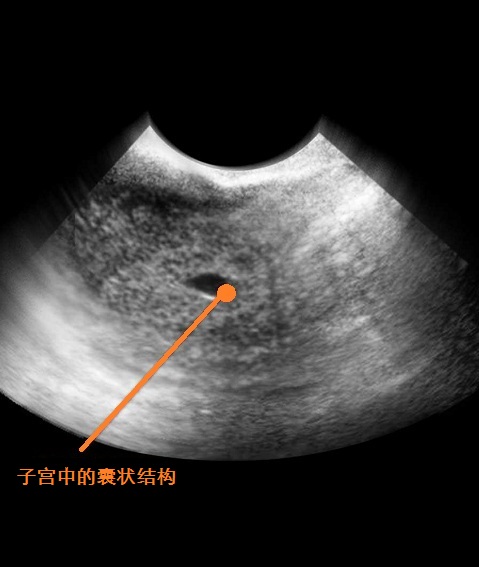

B超图

黄体素问题 怀孕后卵巢开始分泌黄体素,初期妊娠接受超音波检查时,经常看到卵巢长水瘤,这些绝大多数都是属于黄体囊肿,等到妊娠满三个月就会自动消失,如贸然开刀切除,可能伤害胎儿造成流产,因此,不是必要不要开刀。